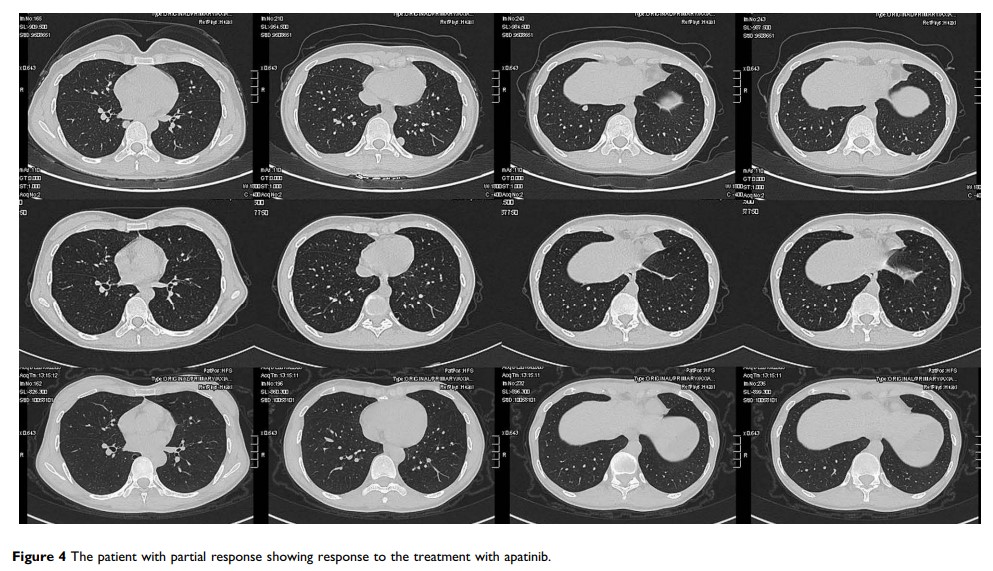

阿帕替尼在晚期滑膜肉瘤中的疗效和安全性:单一机构中 21 位患者的病例系列